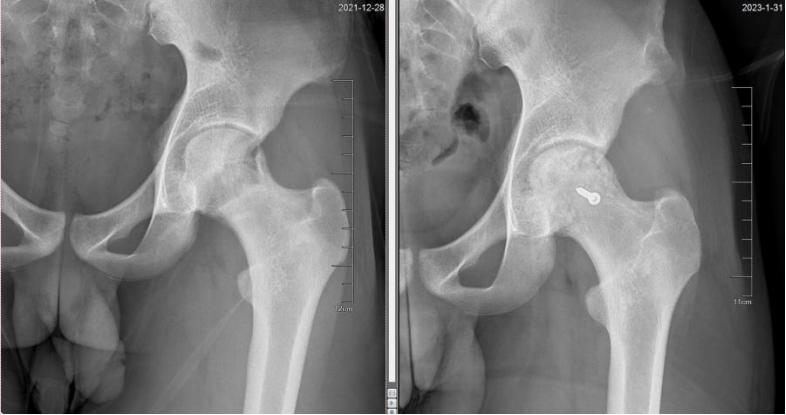

△术前术后X光图对比可见:左侧股骨头坏死修复,头臼匹配

阿峰出院后1.5个月、5个月、半年、9个月、13个月,均严格遵医嘱返院复诊,接受康复指导,术后半年即可恢复行走,术后13个月,阿峰的髋关节基本恢复正常,不仅疼痛消失,而且跑步、下蹲等正常活动都没有问题,复查完毕后,本已离开诊室的阿峰,又心怀忐忑委托母亲咨询何伟教授,能否继续参加踢足球、打篮球等运动,何伟教授给予了肯定的答复,阿峰听说后也露出了久违的笑容。